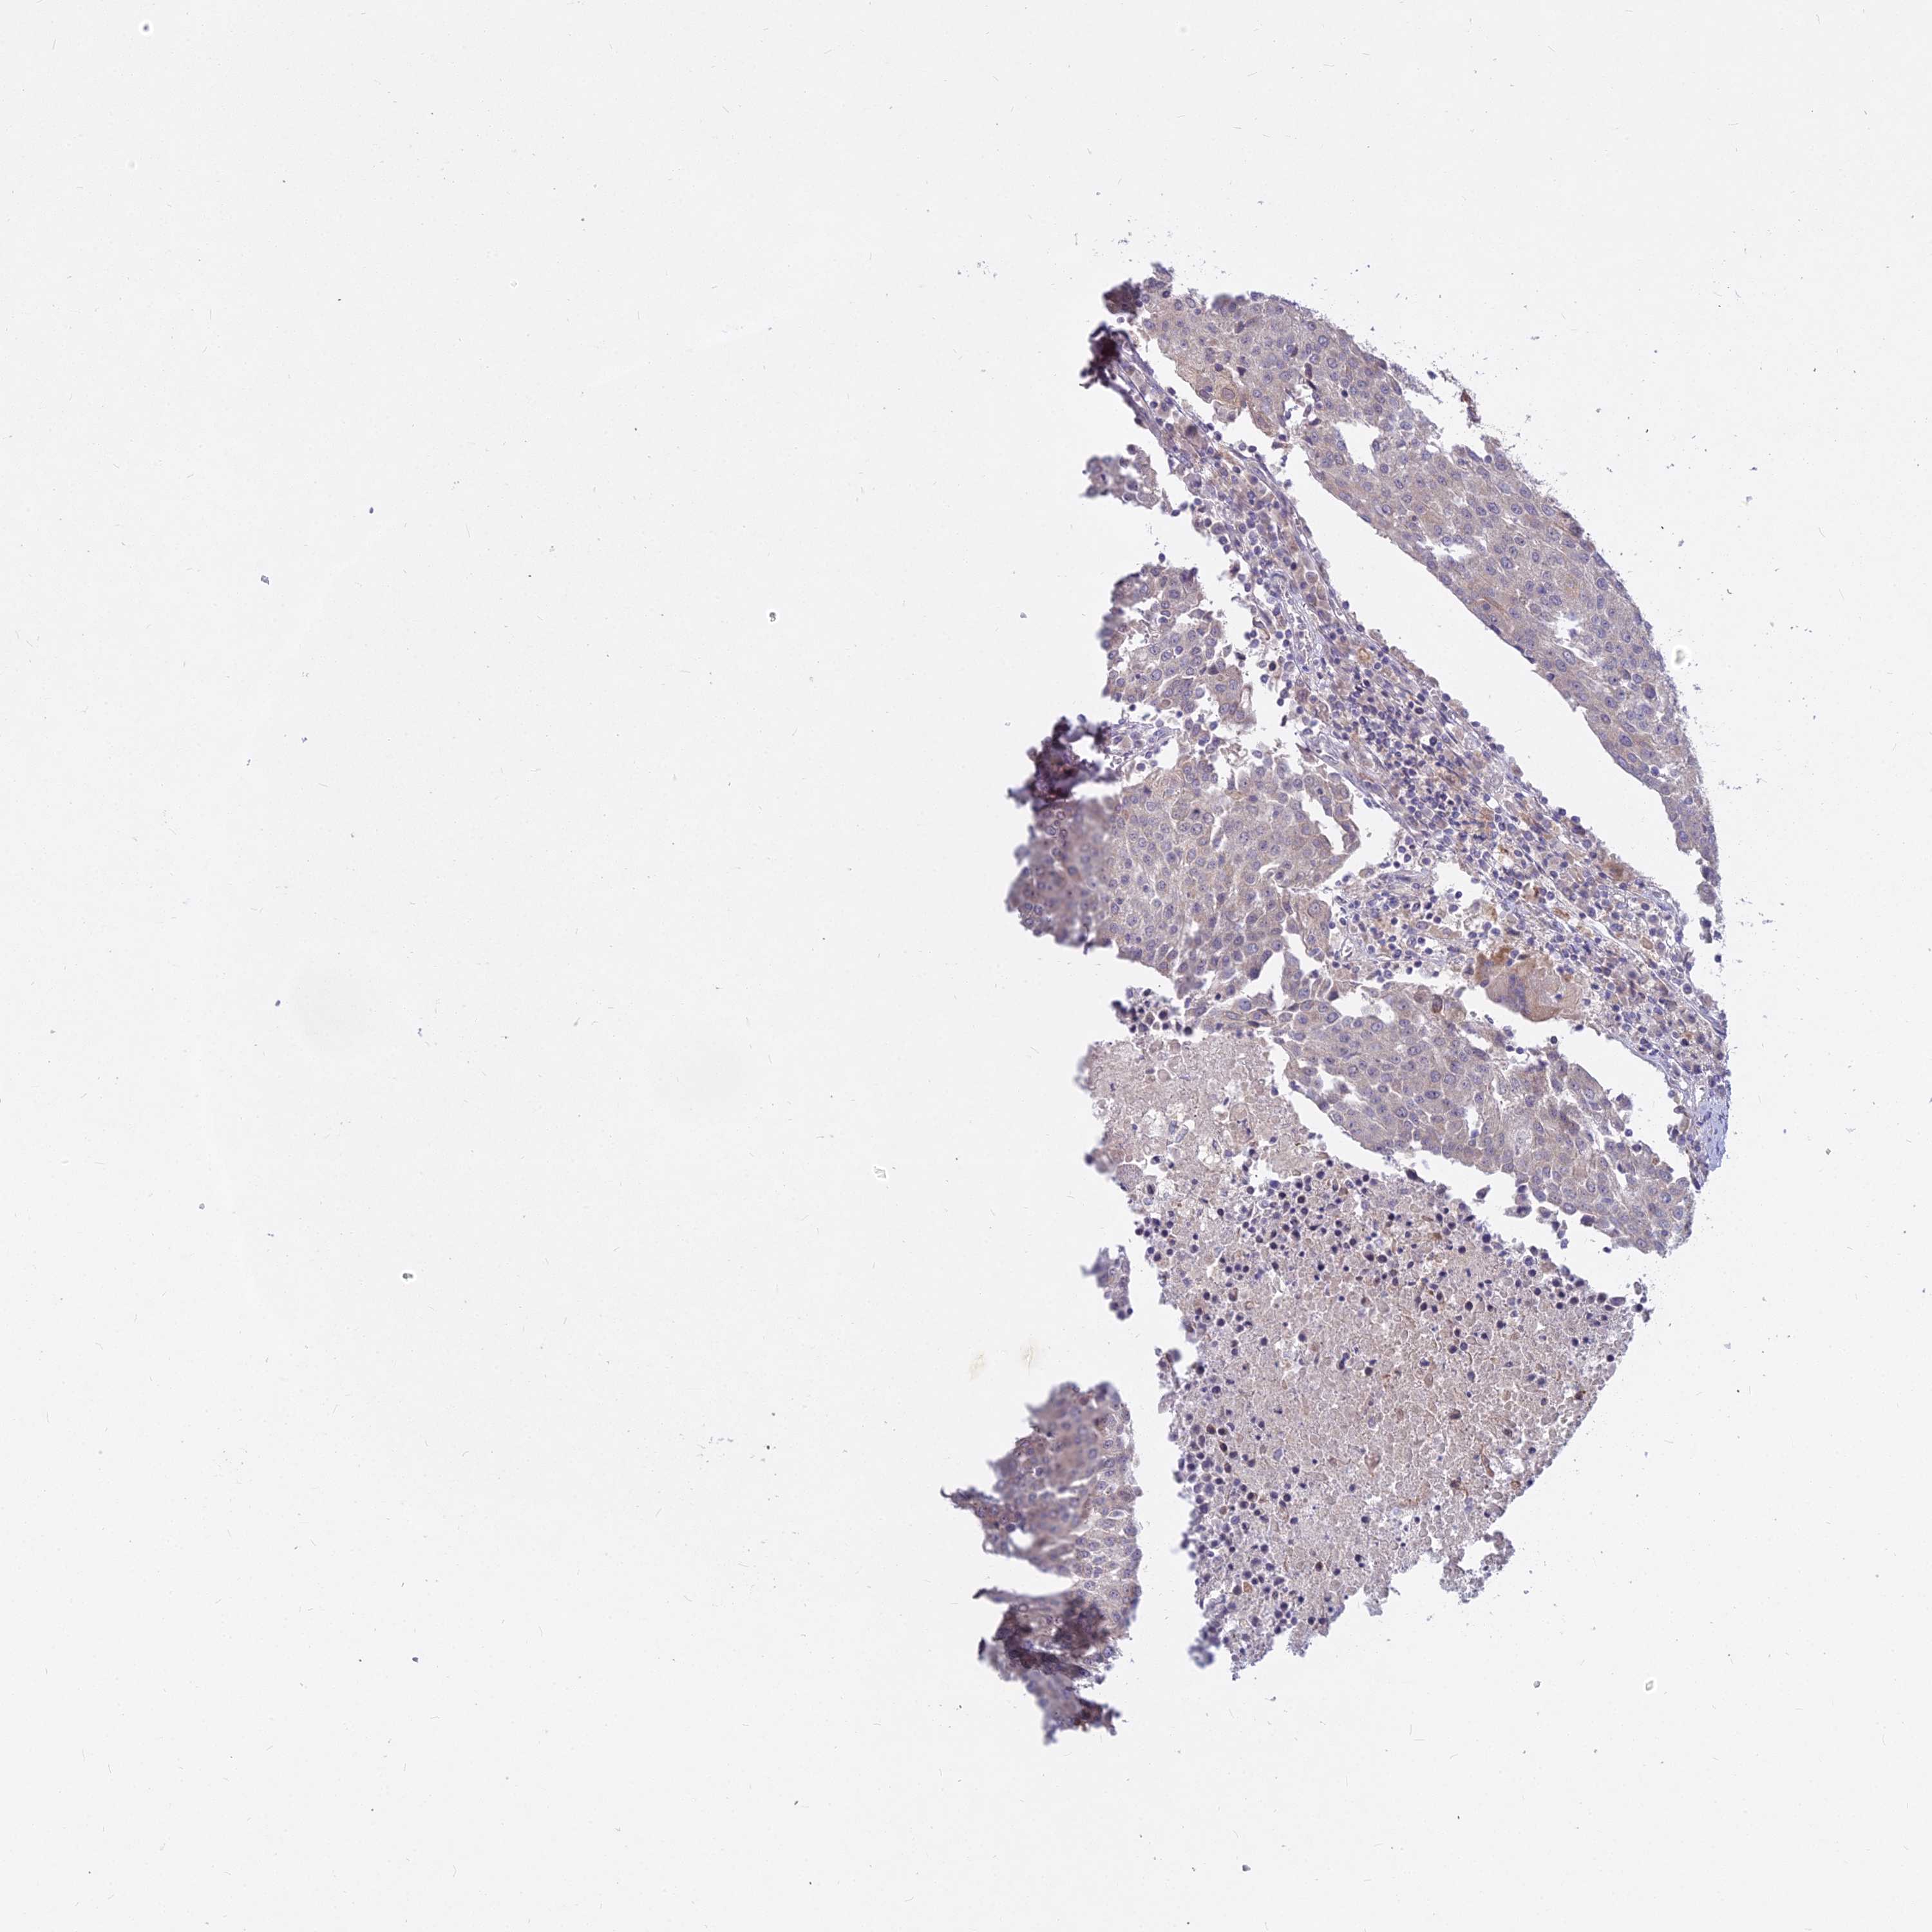

UROTHELIAL CANCER - Protein expressioni

A mouse-over function shows sample information and annotation data. Click on an image to view it in a full screen mode. Samples can be filtered based on level of antibody staining by selecting one or several of the following categories: high, medium, low and not detected. The assay and annotation is described here.

Note that samples used for immunohistochemistry by the Human Protein Atlas do not correspond to samples in the TCGA dataset.

Antibody stainingi

Antibody staining in the annotated cell types in the current human tissue is reported as not detected, low, medium, or high, based on conventional immunohistochemistry profiling in selected tissues. This score is based on the combination of the staining intensity and fraction of stained cells.

Each image is clickable and will lead to virtual microscopy that enables deeper exploration of all samples and also displays staining intensity scores, fraction scores and subcellular localization as well as patient and tissue information for each sample.

Antibody HPA045511

Staining

High

Medium

Low

Not detected

Intensity

Strong

Moderate

Weak

Negative

Quantity

>75%

75%-25%

<25%

None

Location

Nuclear

Cytoplasmic/membranous

Cytoplasmic/membranous,nuclear

Urothelial carcinoma, High grade

Urothelial carcinoma, Low grade